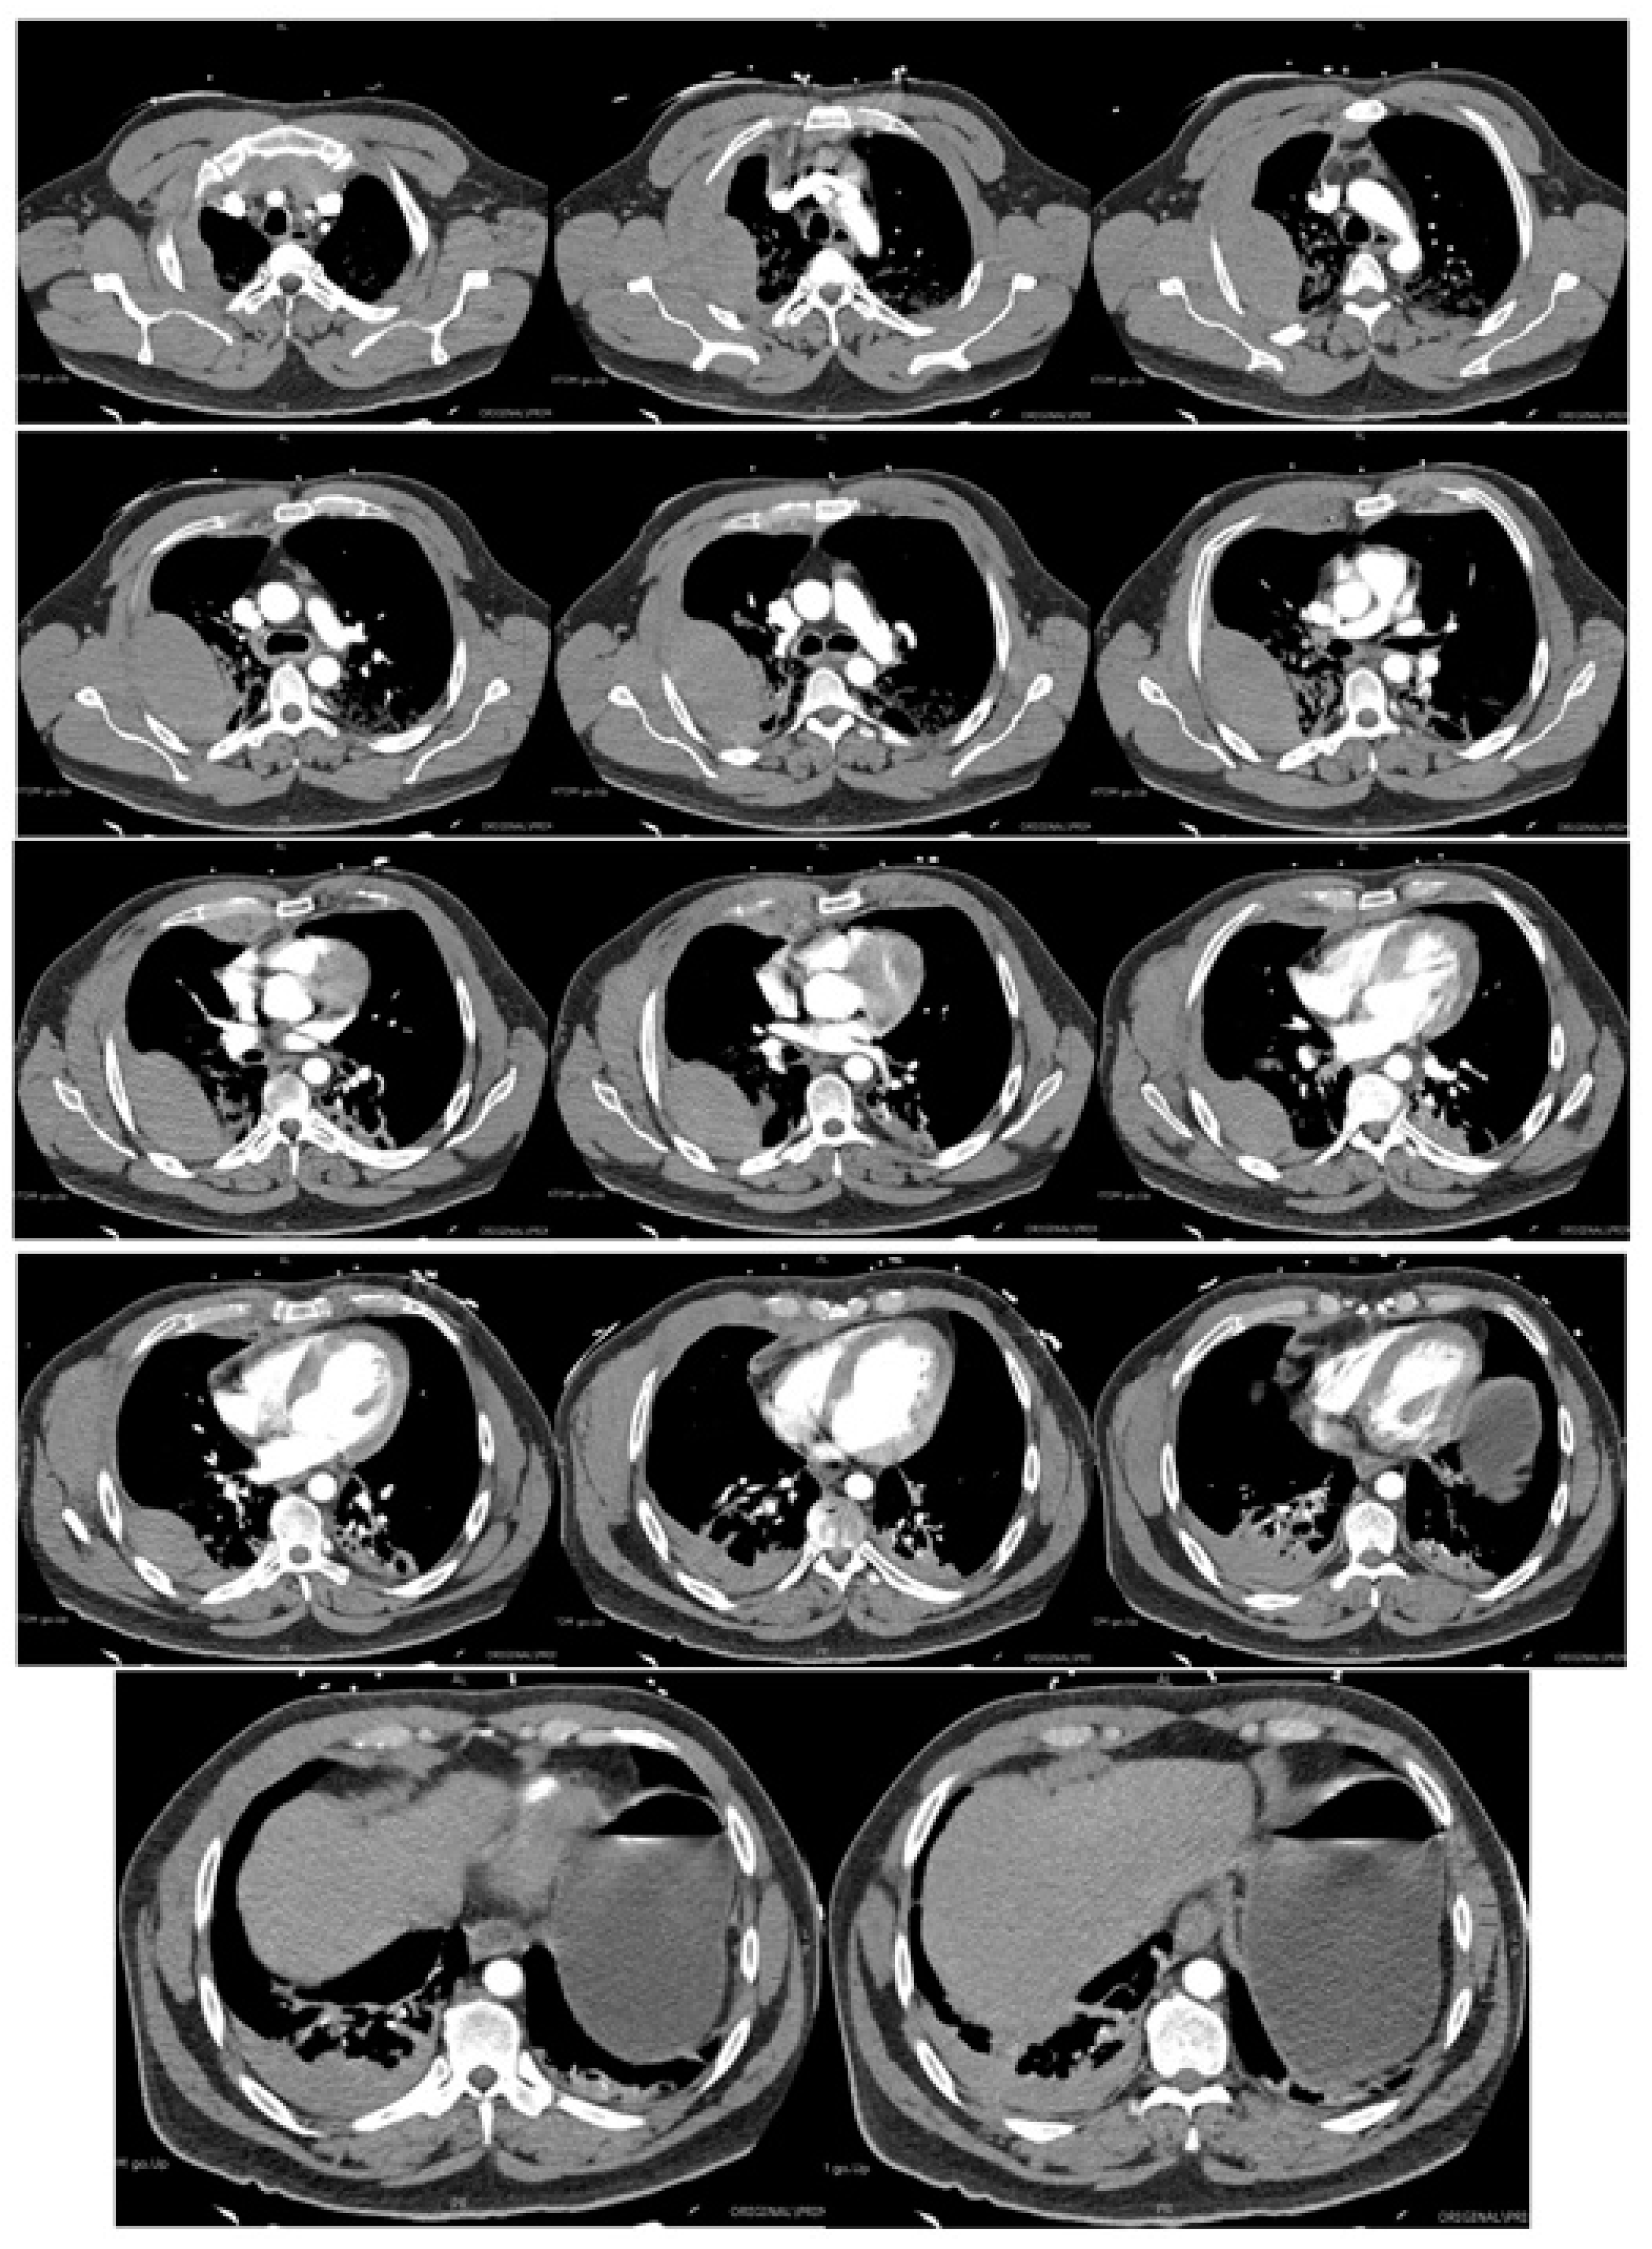

Acutely post-procedure, he complained of a right-sided apical pleuritic chest pain. At this time, his Glasgow coma scale was 15, he was afebrile, with a blood pressure of 132/81 mmHg, pulse rate of 72 bpm, tachypneic at 22 respirations per minute with 94% saturation on room air, and he had bilateral crepitations in his middle to lower zones. A chest X-ray (CXR) was performed immediately; the findings and radiograph are shown in Figure 1. A computed tomography (CT) scan with contrast of his chest was performed shortly after; the images and findings are shown in Figure 2. The concern for the hemothorax was increasing given the active bleed, and that the DAPT should not be stopped under any circumstance, due to high risk of stent thrombosis. A general surgical consult was sought which culminated in the recommendation of a cardiothoracic consult. Throughout this period, regular blood was taken to monitor the hemoglobin levels and for a blood group and matching.

Figure 1. AP erect CXR. Large biconvex right upper chest zone hyperdense lesion. Right lung and left upper lobe contain hazy air space opacity. No pneumothorax. No midline shift. Blunting of right costophrenic angle.